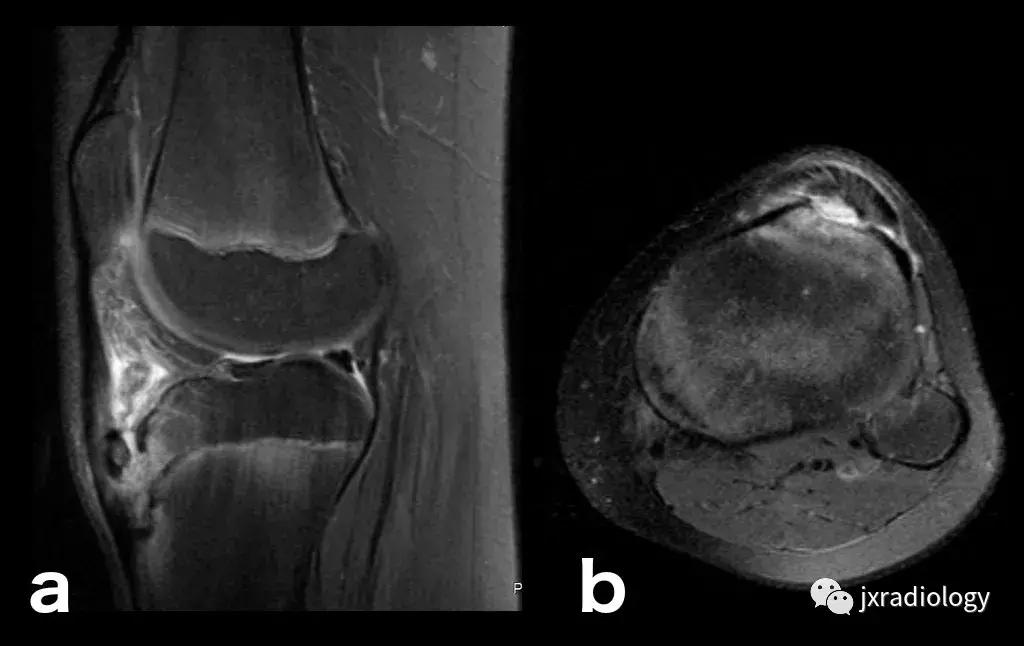

图26:局限性游走性骨质疏松症(具有位置变化的短暂性骨髓水肿综合征)(连续冠状PD-FS-WI):在一些情况下,在连续MRI上看到骨髓水肿的位置变化,这被称为局限性游走性骨质疏松症(RMO);尽管可以自愈的短暂性骨髓水肿综合征的情况更为常见,但可以在一小部分病例中转移到不同的关节,或者(甚至更罕见)转移到同一关节内的不同部位(关节内转移) ,如关于该患者所见。在这个关节内RMO病例中,没有创伤史,水肿始于股骨内侧髁,3个月后发现转移到外侧髁。

图28:正常的红骨髓:这是寻找骨髓水肿时可能出现的误区。造血系统红骨髓(由于年轻患者正常分布或成人骨髓再生)在T1-WI(b)和水敏序列(a:PD-FS-WI)上均具有中等信号强度。T1-WI上的正常红骨髓相对于肌肉的分布(通常在干骺端)的特征性模式和较高的信号强度(与T1-WI上肌肉组织的等信号或低信号的病理性骨髓相反),应能及时发现这一正常发现。